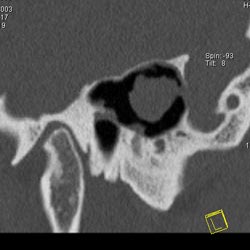

Рис. 10. Принципы КТ высокого разрешения (КТВР) на примере исследования пирамиды височной кости. Применены тонкие срезы (0.5 мм) и "острый" алгоритм реконструкции (кернель 90). (Слева) отчетливо видны элементы внутреннего уха - улитка, полукружные канальцы. (В центре) показана проекция продольного сечения височно-нижнечелюстного сустава. (Справа) - холестеатома.